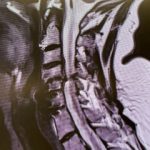

(Fig. 1) Sagittal T2 cervical MRI demonstrates significant C34 and C45 disc degeneration and osteophyte formation and instability status post anterior cervical discectomy and fusion C5-C7.